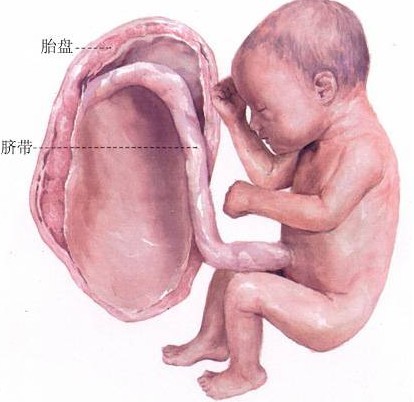

怀孕四个月胎儿彩超

胎儿没什么问题建议不要做B超。这个不好排除,做彩超也只能看胎儿肢体和器官发育而已对大脑跟本没办法了解所以你要好好养胎生下就知道了一般来说不会有什么问题的

我怀孕八个月了还没做过四维彩超现在八个月还有必要做吗?大概多少钱? 收藏 答案(4) 做应该好做的,不过我们当时检查的时候医生说有些畸形筛查过了24周四维就查

已经8个月了,医生建议可以去做个胎儿心脏检查,是四维彩超,不知道是不是只要是8--9个月之间都可以,会不会对胎儿有影响!

您好,现在都已经是8个月了,做四维彩超没有什么意义了。指导意见:都快到预产期了可以做个普通的彩超就可以确定是否对孩子产生影响的。因该是不会有什么问题的。

怀孕六个月做四维彩超发现胎儿左侧眼球内下 怀孕八个月做四维彩超显示胎儿双顶径只有6 我现在怀孕五个月做四维彩超结果说小孩8两 怀孕六个月做四维彩超一切正常就

怀孕八个月做四维彩超显示胎儿双顶径只有6.9cm,股骨长5,7cm,双顶径太小了怎么办? 怀孕八个月做四维彩超显示胎儿双顶径只有6.9cm,股骨长5,7cm,双顶径太

我怀孕到现在快8个月了没做过四维彩超,就做过产前筛查,还需要去做四维彩超吗?大概需要多少费用?我怀孕到现在快8个月了没做过四维彩超,就做过产前筛查,还

我现在怀孕五个月做四维彩超结果说小孩8两,大夫说小孩小,到底多重正常 怀孕六个月做四维彩超胎儿后颅窝池深0。7 怀孕五个月做四维彩超能看到孩子的